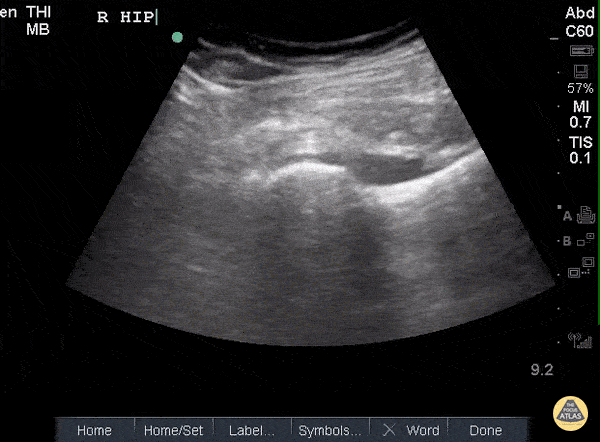

POCUS of the R hip shows an anechoic region adjacent to the femoral head and within the joint capsule consistent with an effusion. Sukh Singh, MD